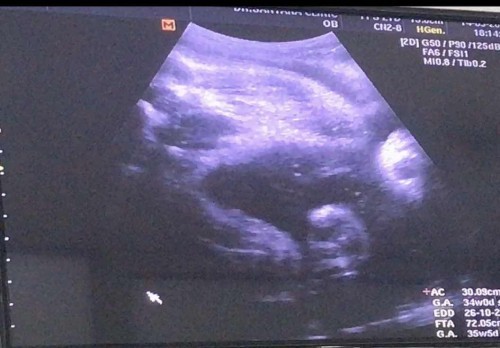

คุณแม่ที่หมอนัดกระตุ้นคลอด ใช้เวลากี่วันค่ะถึงจะคลอดค่ะ พอดีกำหนดคลอดวันที่5ตุลา แต่หมอนัดกระตุ้น28กันยานี้ค่ะ อยากทราบว่าคุณแม่ที่กระตุ้นคลอด กระตุ้นแล้วอีกกี่วันถึงจะคลอดค้ะ ขอบคุณคร้า

ของเรา 8 ตุลา หมอนัดกระตุ้น 24 กันยา ตื่นเต้นมากกกกกก ถามเพื่อนๆ เห็นบางคนบอกกระตุ้นแล้วเป็นอาทิตย์กว่าจะคลอด บางคนก็บอกโดนกระตุ้นหลายครั้ง บางคนก็บอกกระตุ้นตอนเย็นอีกวันคลอดเลย ตอนนี้แม่เลยเตรียมใจเผื่อคลอดไว้ทุกวันเลย 🤭